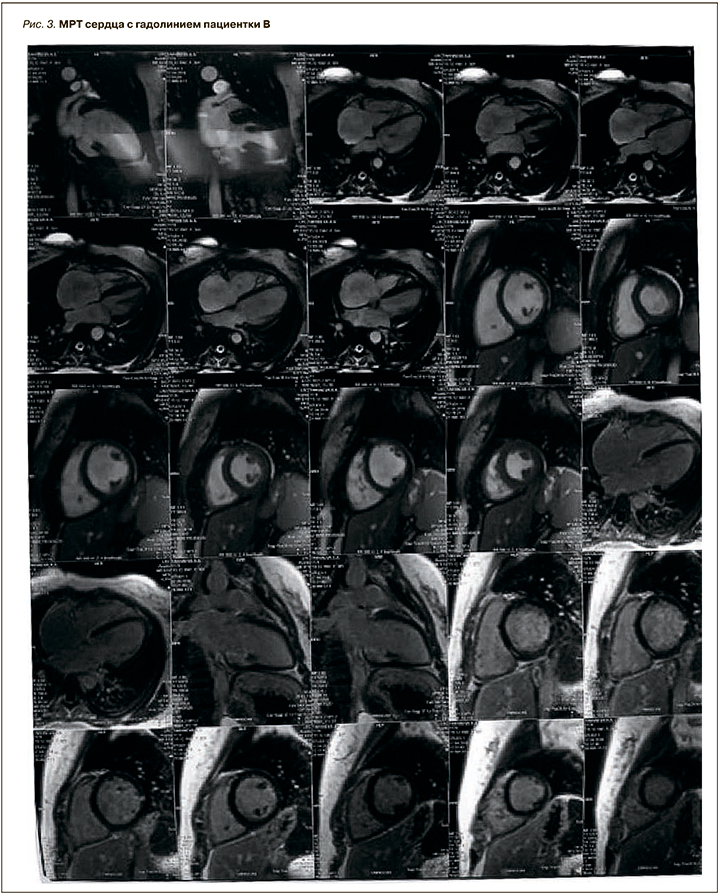

МРТ сердца с контрастированием. Небольшой интрамиокардиальный участок фиброза в миокарде ЛЖ, возможно поствоспалительной природы. Данных за расширение ЛЖ не получено (размеры ЛЖ в 4-камерной проекции: 3,4×5,2 см, левого предсердия – нет данных), сократимость ЛЖ не снижена. Размеры правого желудочка в 4-камерной проекции 3,4×5,2 см, правого предсердия 6,3×7,1 см. Заключение: расширение правого предсердия, трикуспидальная регургитация 2 степени (рис. 3).